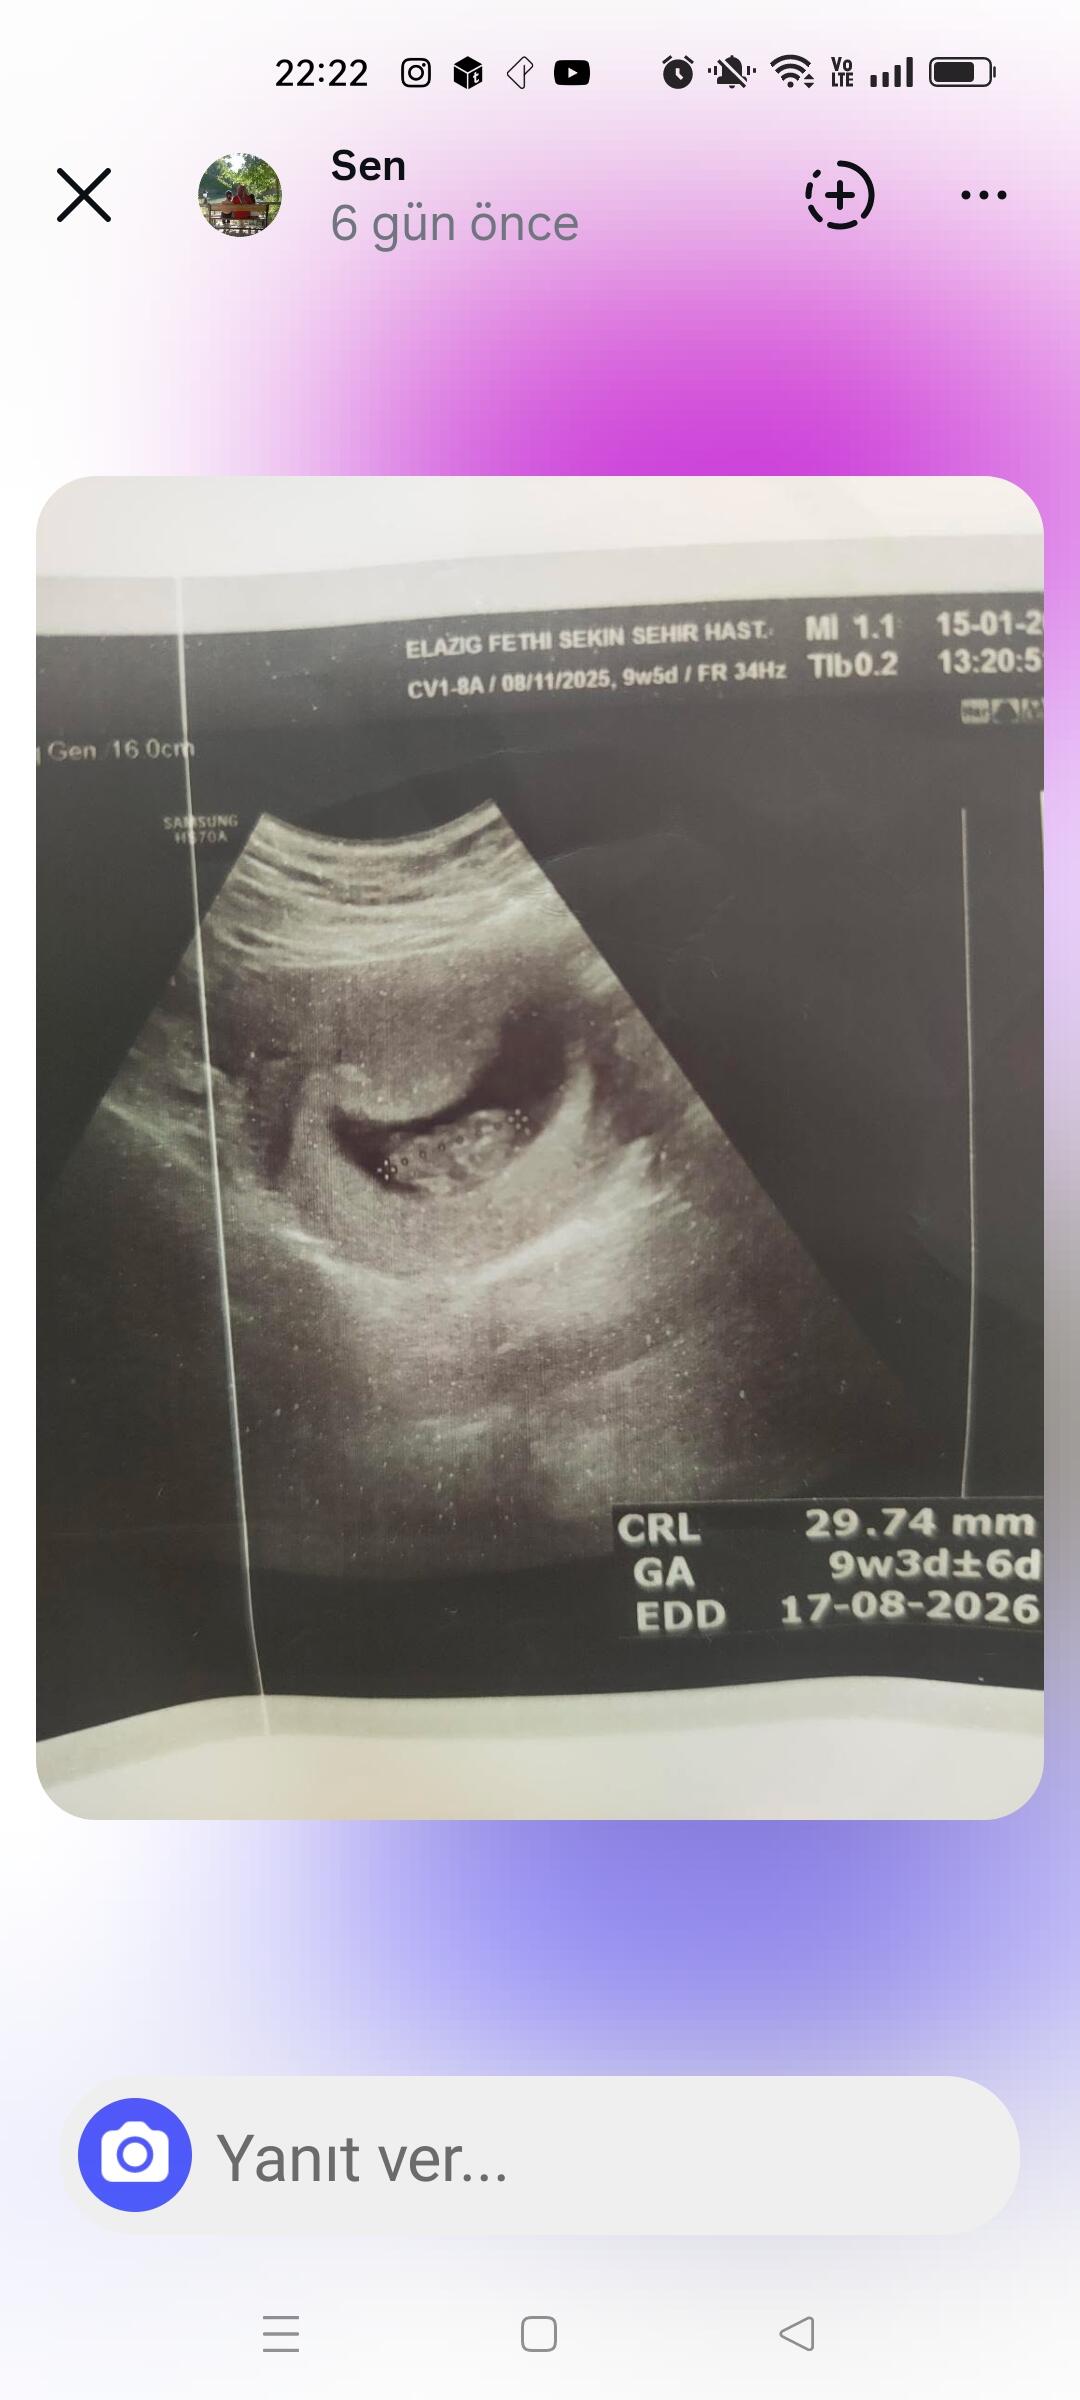

Aynı benimkine benziyo bana kız dediler sorduğumda bizde emin değiliz diyolar bakalm hayırlısı kız diye biliyorum

Chat gpt sordun mu bana seninki net kız gibi geldi ama kendime fikir yürütemiyorum

Nub teorisine göre yorumla de

Şimdi sordum çok net değil ama kız gibi dedi bu çok öncesinin fotoğrafı 12 haftalıkken çekilmişti en son olan fotoğraf doktorun kendisinde bakalm bu sefer daha net söyler inşAllah

At cnm kaç haftalık oldu

Attımm bakar mısınızzz

Kız bence ya

Erkek gibi duruyo canim Allah bilir yine de boylu boyuna da yatiyo maaşallah Rabbim sağlıklı sıhhatli kucagina almak nasip etsin insallah canım

Kız gibi dedi Nuba göre

Erkek bebiş kuzum

Erkek gibi geldi bana da hayırlısını versin rabbim insallah canim allah sag salim sağlıklı bir sekilde kucagina almak nasip etsin insallah